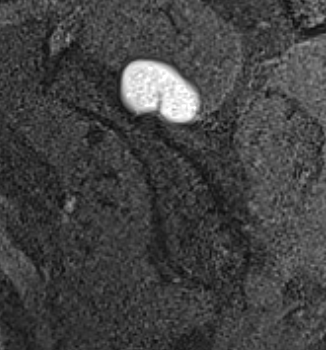

Spinoglenoid Cyst

MRI

Spinoglenoid cyst with SLAP tear and posterosuperior labral tear